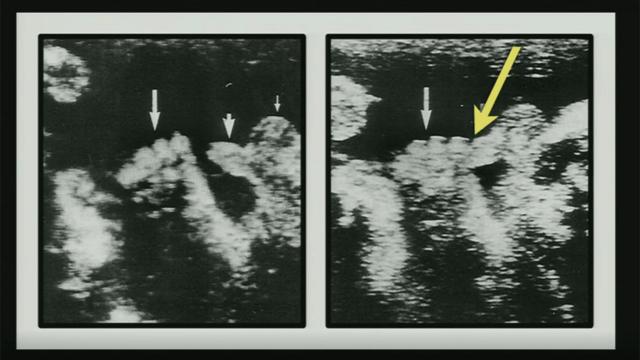

galera bet aplicativo "Eu vou mostrar para vocês algumas imagensgalera bet aplicativoum estudo muito divertido do Journal of Ultrasound Medicine. E me aventuro a dizer que é o artigo mais divertido já publicado no Journal of Ultrasound Medicine. O título é 'Observaçõesgalera bet aplicativoMasturbação Intrauterina'."

Na sequência, Mary Roach projeta uma ultrassonografia na parede do palcogalera bet aplicativoque se vê claramente um feto segurando o pênis com a mão.

Não se esqueçam que é uma ultrassonografia, então "as imagens deveriam apresentar movimento", acrescenta a jornalista americana especializadagalera bet aplicativociência, lançando mãogalera bet aplicativosua veiagalera bet aplicativocomediante para entreter a plateia, que ainda não decidiu se deve rirgalera bet aplicativovoz alta ou levar o assunto a sério.

A ideiagalera bet aplicativoRoach era encorajar as pessoas a falar abertamente sobre sexo/ acima, a ultrassonografia que apresentou